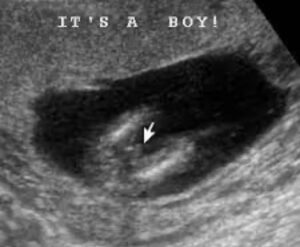

يستطيع الطبيب المساعدة على تحديد نوع الجنين بالبحث عن شكل اعضاء الجنين الذكر والتي تظهر في تصوير السونار بشكل غطاء السلحفاة وتسمى علامة السلحفاة turtle sign كما يتضح في الصورة التالية.

وفيما يلي بعض صور السونار التي يمكن ان تساعدك على التفرقه بين الاجنة الذكور والاناث في تصوير السونار.